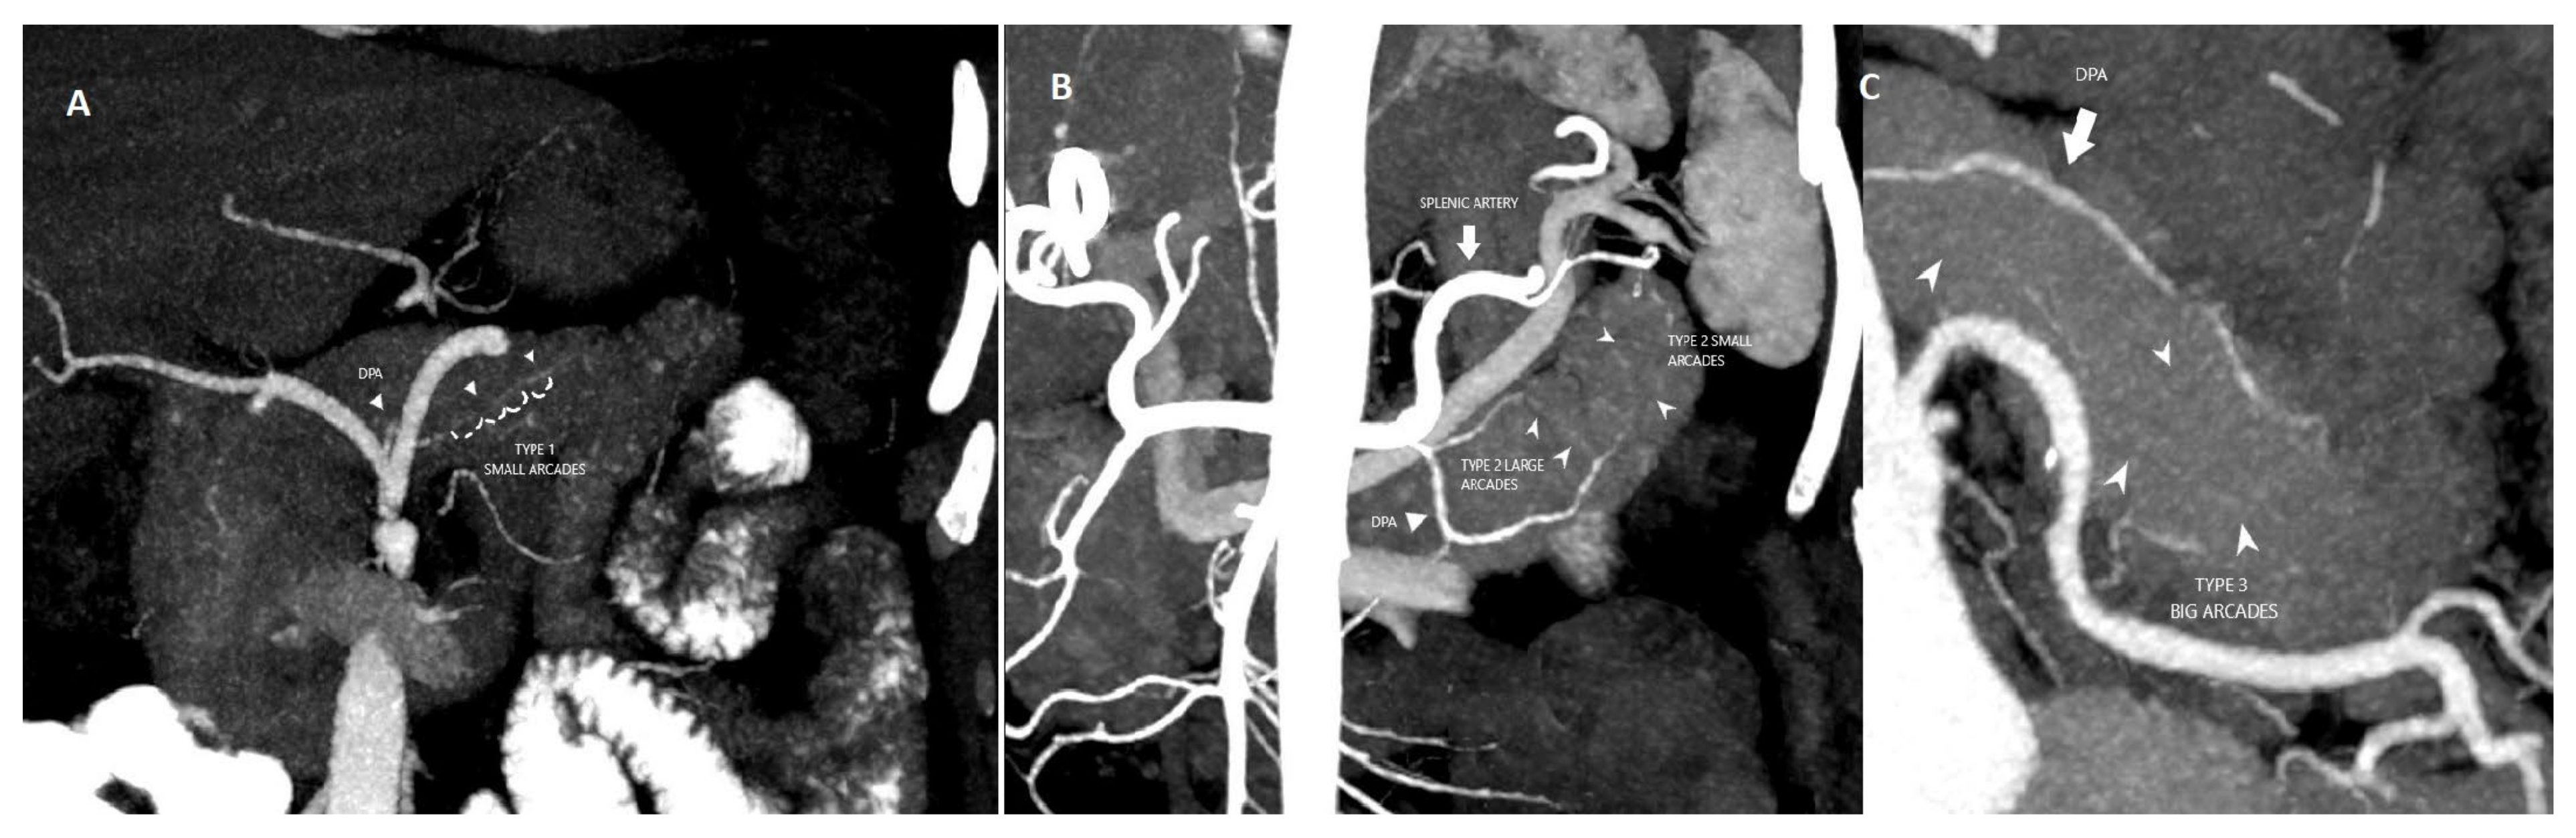

Readers were tasked with assessing the following variables: (a) origin of the DPA and (b) intrapancreatic arcade classification type. The origin of the DPA was evaluated (Figure 1). Previously, the anatomy of the intrapancreatic arcade has been categorized into four types: type 1 (minor arcades), type 2 (minor and major arcades), type 3 (major arcades) and type 4 (straight branches) according to Roman Ramos et al. [18]. The intrapancreatic arcade anatomy was grouped according to this classification (Figure 2)

Figure 2.

(A) Coronal MIP image shows type I pancreatic arcade with multiple small branches. (B) Coronal MIP image shows type II pancreatic arcade with small and large branches. (C) Coronal MIP image shows type III large pancreatic arcades.

The intrapancreatic arcade was observed in 25% (71/284) of patients. The distribution of arcade anatomy was as follows: 28.2% (n = 20) arcade type 1, 49.3% (n = 35) arcade type 2 and 22.5% (n = 16) arcade type 3 (Figure 2). Arcade type 4 anatomy was not detected. The mean follow-up time in this group was 31.85 ±19.59 months. The 90-day mortality and long-term mortality rates did not differ among the groups in this group (p ≥ 0.05). The presence of POPF was significantly different between the groups (p = 0.042); a higher proportion of POPF was observed in group 3 (Table 2) (Figure 3). There were no significant differences between the two groups with regard to gender distribution, the presence of systemic disease, or the length of hospitalization (Table 2).

In some previous studies, ligation of the DPA has been reported to reduce bleeding during DP. Jiang et al. reported that ligation of DPA before dissection of the uncinate process improved resection time and blood loss in laparoscopic PD [34]. The right branch of the DPA supplying the pancreatic head is considered as one of the efferent arteries of the pancreatic head [26]. Studies have focused on the risk of intraoperative hemorrhage but have not sufficiently focused on the postoperative perfusional risks of the pancreas. In DPA arcade type 3, vascularization is provided only by the long branches of the SA [18]. We predict that the less branching in type 3 compared to other types may lead to insufficient postoperative pancreas vascularization. Considering the relationship between blood loss and pancreatic fistula, we think that malperfusion may indirectly lead to POPF development.